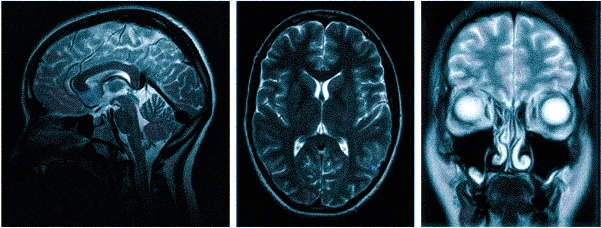

МРТ при головных болях (в трех проекциях): специальная программа выстраивает объемные изображения полученных срезов, что позволяет увидеть даже мельчайшие изменения и отдифференцировать патологию от нормы

Причин головной боли множество, и их не всегда возможно определить без помощи современных способов визуализации. Цефалгию вызывают: повышенное внутричерепное давление, сосудистые мальформации, опухолевые процессы, постравматические осложнения. Какую МРТ делать при головной боли или предпочтительней пройти КТ — зависит от предполагаемого характера патологии. Все методы являются взаимодополняющими, но что лучше в конкретном случае, выбирает врач с учетом жалоб, показаний и противопоказаний. МРТ и КТ с контрастным усилением позволяют получить сопоставимые по качеству снимки, но при этом используют разные принципы построения изображений. Чем раньше будет найдена причина и проведено адекватное лечение, тем больше шансов на полное выздоровление.